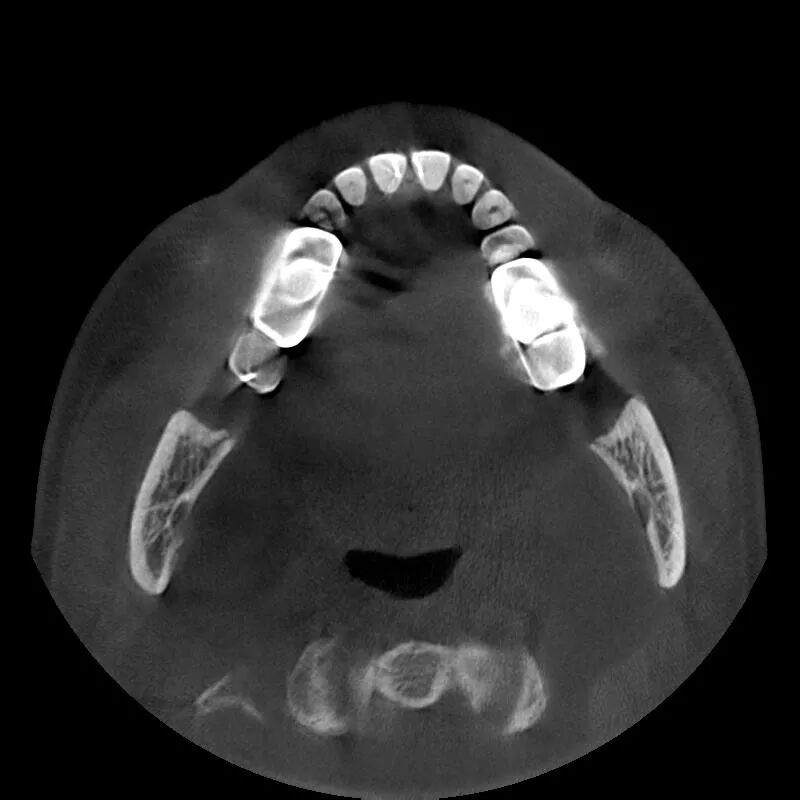

“伯爵Bondream”智能3D全景CBCT 多金屬去偽影圖

普通CBCT 多金屬去偽影圖(同一患者)

上頜竇底,骨小梁與下頜神經(jīng)管清晰可見(jiàn)

植體周圍無(wú)陰影,植體螺紋清晰可見(jiàn)

清晰的3D影像為實(shí)現(xiàn)數(shù)字化精準(zhǔn)治療保駕護(hù)航

骨密度精確測(cè)量